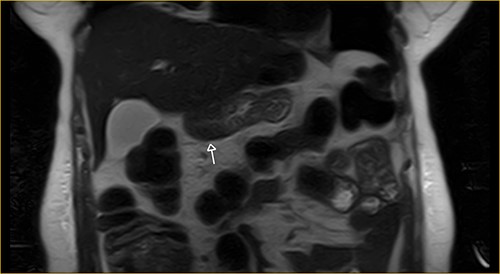

Laboratory examination showed anemia. An excluded stomach distention and parietal thickening of the pylorus and antrum were identified during abdominal computed tomography (CT) and magnetic resonance imaging (Figs 1–4). Thoracic CT was normal.

Transversal section on T2-weighted magnetic resonance showing excluded stomach distention with parietal thickening of the pylorus and antrum (arrow).